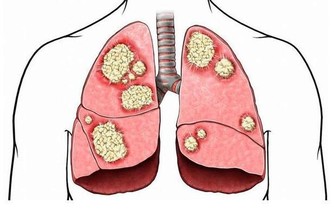

這是因為氧化應激與細胞癌變息息相關,

人體缺硒時無法阻攔氧化應激對細胞帶來的損傷,進而會增加罹患癌症的風險。

德國一個研究所對此展開了研究,結果發現缺硒會使肝癌的發病率提高10 倍。